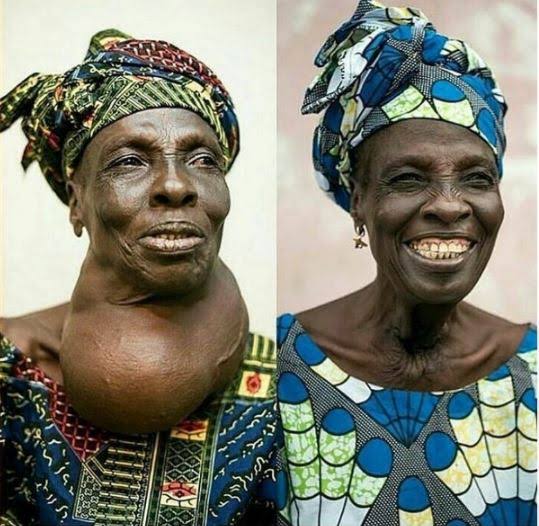

Is your neck gradually swelling up? Is it making you feel so uncomfortable? This is called goitre and it can happen to anybody.

It can also be treated if you are ready to get the solution.

Your neck will start going down and you will be alright within 30 days

Goitre Ender Tea is the herbal product that thousands of Nigerians are using to cure all type of throat, mouth and neck problems.